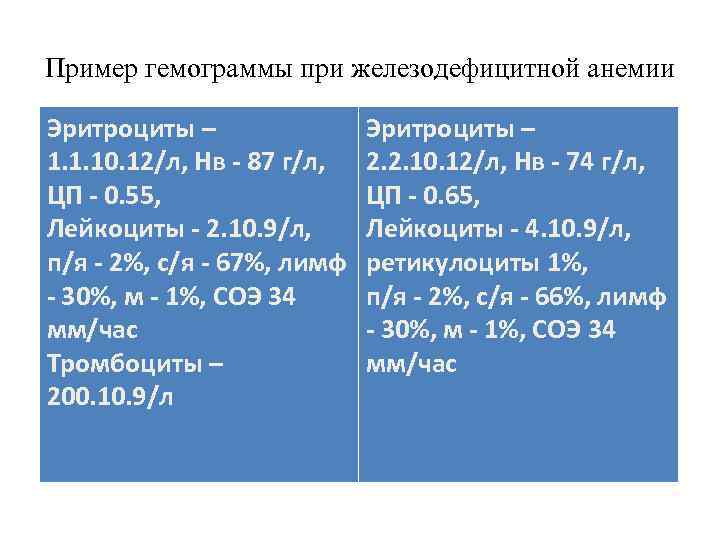

Пример гемограммы при железодефицитной анемии Эритроциты – 1. 1. 10. 12/л, Нв - 87 г/л, ЦП - 0. 55, Лейкоциты - 2. 10. 9/л, п/я - 2%, с/я - 67%, лимф - 30%, м - 1%, СОЭ 34 мм/час Тромбоциты – 200. 10. 9/л Эритроциты – 2. 2. 10. 12/л, Нв - 74 г/л, ЦП - 0. 65, Лейкоциты - 4. 10. 9/л, ретикулоциты 1%, п/я - 2%, с/я - 66%, лимф - 30%, м - 1%, СОЭ 34 мм/час